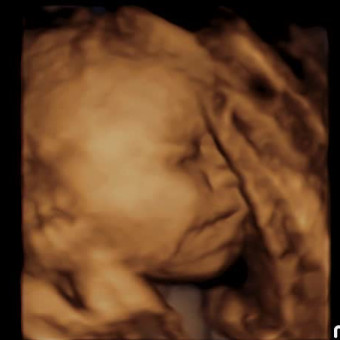

Baby Ariella’s Registry 💌

Halo Aparicio & Armando Roman

March 22, 2026